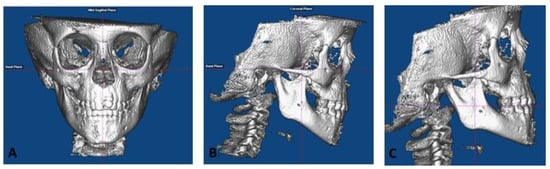

- Roll: The cranium was oriented such that a midline could be drawn through the midpoint of the frontonasal suture and base of the nose and is parallel to the true vertical (Figure 1A). In addition, a true horizontal line goes through the most inferior aspect of the orbits.

- Yaw: The cranium was oriented to achieve the best symmetry of the cranium, zygomatic, and maxillary structures on either side of the midline (Figure 1A).

- Pitch: For measurements on the non-tooth-bearing, skeletal features of the face, the cranium was oriented such that the Frankfort horizontal plane was parallel to the true horizontal plane (Figure 1B). For measurements on the tooth-bearing, dentoalveolar areas, the cranium was oriented such that the functional occlusal plane was parallel to the true horizontal plane (Figure 1C).